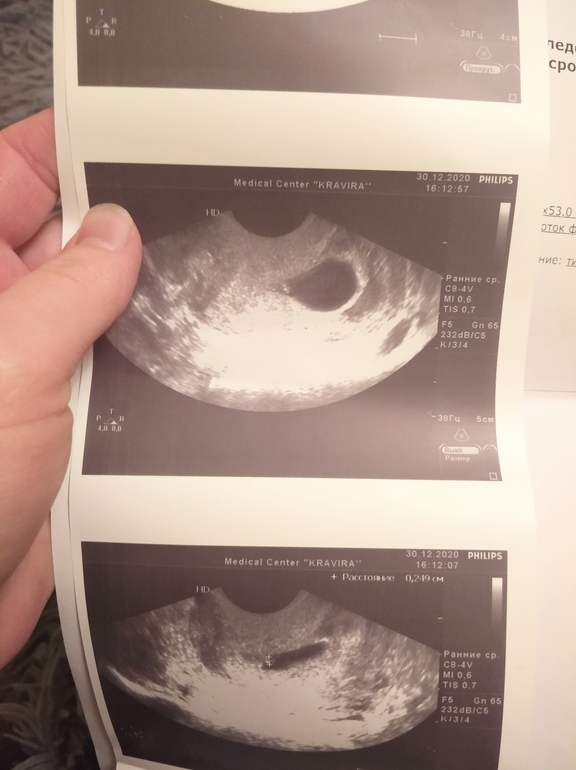

Сходила всё-таки на УЗИ из-за болей справа. Срок 5н.6дн по приложению

Нашли нас в матке, ПЯ 22, эмбрион 2 мм, С/Б определяется.

Единственное- эмбрион расположен сбоку плодного яйца, кровоток определяется примерно в районе желточного мешочка или даже за ним. Врач намекнула на это и сказала, что не знает почему так. Контроль УЗИ через 2 недели